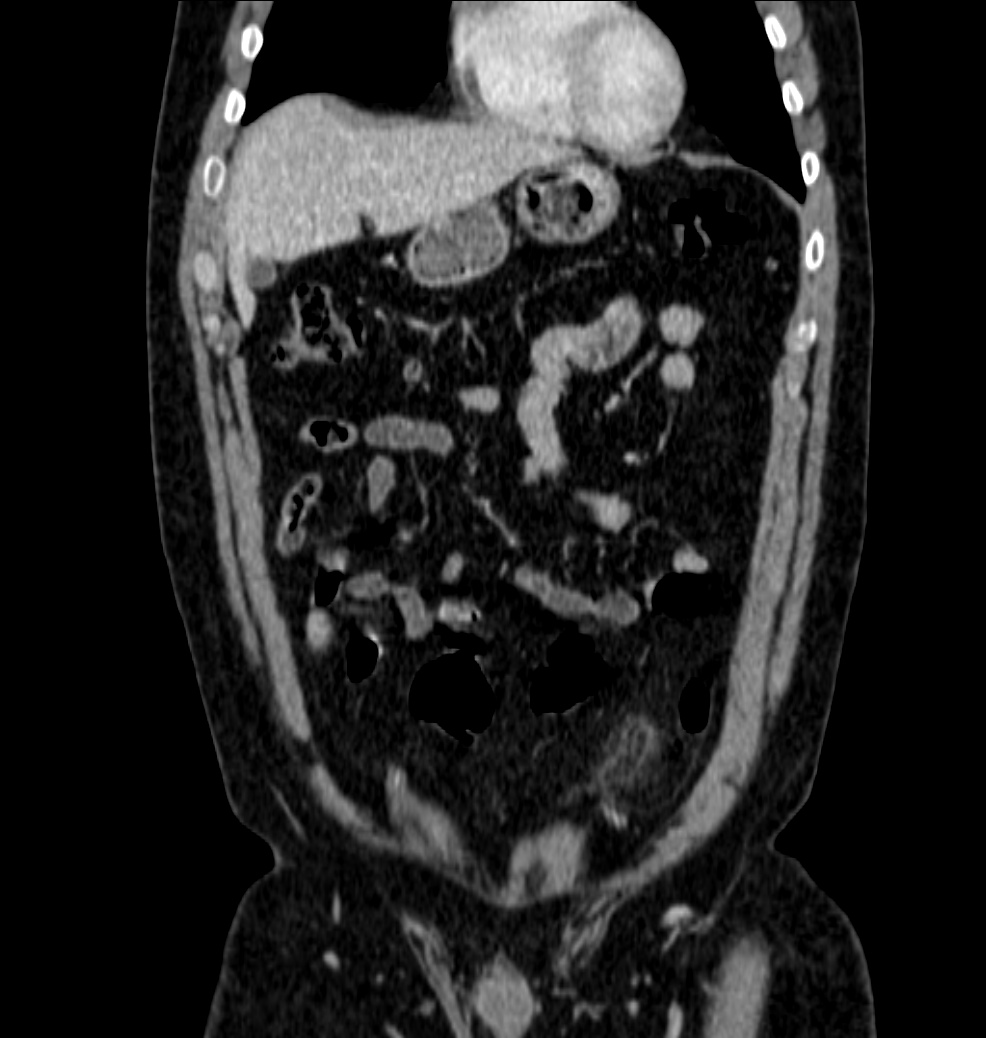

Ante la persistencia del dolor, el elevado IMC del paciente y la necesidad de descartar patología de FID, apendicitis, se decidió realizar TAC de abdomen:

Nos enfrentamos a un poceso que afecta el Epiplon, más concramente un apéndice (o colgajo) del mismo, compuesto por grasa y vasos que se inflaman por compromiso vascular venoso. Se denomina Apendagitis y lo podemos confudir, entre otras entidades, con una apendicitis.

TAC: Imagen oval con aumento de la atenuación central, inferior a 5 cm de diámetro, contigüa al colon, con afectación de la grasa periférica. El aumento de la atenuación central es un signo de trombosis venosa muy útil para el diagnóstico, pero su ausencia no excluye en diagnóstico de apendagitis. Otros hallazgos, como aumento de la pared colónica o formación de abscesos son raros. Aunque los síntomas remiten en dos semanas, los cambios en la TAC pueden prolongarse más tiempo (pueden mantenerse, disminuir o quedar una atenuación residual), aunque en 6 mese suele haber remitido completamente. En Ecografía suele observarse en el área de máxima sensibilidad al dolor, una masa hiperecogénica, inferior a 5 cm, no compresible, adyacente al colon y sin señal Doppler.